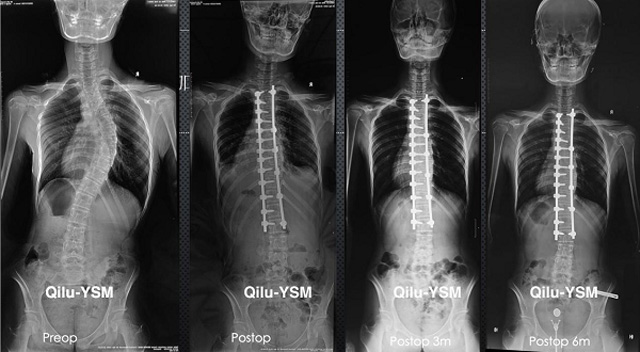

當出現急性外傷或難以控製的慢性疼痛懸吊DR檢查是觀察骨骼簡便的檢查方式,懸吊DR與傳統X線機的區別在於使用相片需要洗片跟數碼存儲數字化,還能進行後期處理分析醫生一般會建議行DR檢查,來判斷是否骨折或者其他情況。 懸吊DR檢查因大大提高了圖像質量,降低了曝光量;成像速度快,工作流程短;圖像動態範圍大;圖像後處理功能強;PACS更強大。適用於人體各部位的健康普查及疾病檢查等優勢,對人體的傷害要更小一個最大的優點,DR的射線量遠小於傳統X線機,在臨床基礎檢查中備受醫生和患者的青睞。

懸吊DR-全電動型機架DR檢查主要用於胸部、四肢、關節、脊柱等,主要檢查肺部炎症、腫瘤、結核病、四肢骨關節的骨折、四肢關節、脊柱外傷等。DR就是X光,是一種數碼影像,曝光時間很短,攝像量很小,影像質量也很好,可以說是一種替代CR的方法。DR檢查有其局限性,需要做CT平掃等檢查,周圍淋巴結的轉移以確定病變的良惡性、範圍、大小、與鄰近組織的關係。